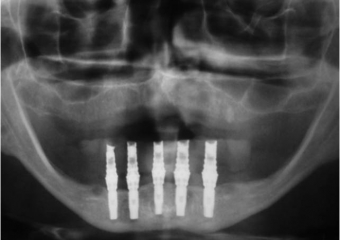

Raio X com os implantes instalados